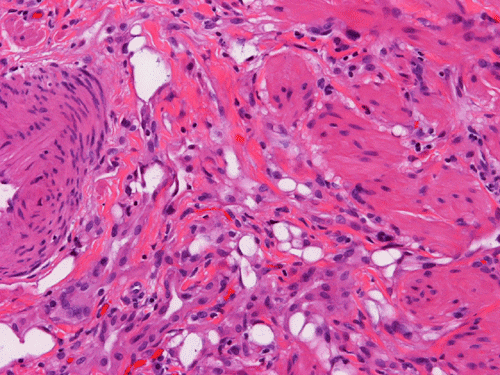

On scanning magnification, there is a round lesion in tissue around the fallopian tube (arrows in Panel A). The lesion does not invade into the tube nor distort or compress the tube. The cross sectional dimension is about the same diameter of the fallopian tube. On low and medium magnification, the lesion is composed of a collection of small microcysts intermingled with the smooth muscle bundles of the wall of the fallopian tube (Panel B and C). On higher magnification, the cyst or gland like spaces are lined by epithelioid to spindle cells with bland nuclei and an abundant amount of amphophilic cytoplasm (Panel D and E). The spindle cells are positive for calretinin, cytokeratin 5/6, and inhibin (Panel F, G, and H).

Histologically, the salient feature is small, microcystic or gland-like cystic spaces lined by flattened cells. Some of the tumor cells may arrange in cords and tubules.  Hyaluronic acid rich material that can be easily demonstrated by Alcian blue stain are present in the small glands and cysts. The tumor cells are medium in size and contain moderate to abundant amphophilic to eosinophilic cytoplasm. Prominent cytoplasmic vacuoles that suggest signet ring cells may be present. This is an important feature to know in order not to confuse these tumors with primary and metastatic carcinomas particularly when the specimen is obtained from the ovary. Although these tumor appears well-circumscribed on gross examination, these tumor appears infiltrative on microscopically and should not be confused with adenocarcinoma. The key to avoid this pitfall is that adenomatoid tumor have bland nuclear feature and no mitotic figures. Infaction can occur in adenomatoid tumor.